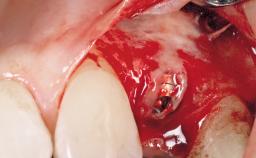

Late Placement of an Implant in a Maxillary Left Central Incisor Site

A 36-year-old female patient was referred for the replacement of the upper left central incisor (tooth 21), which had fractured. Although the tooth had been asymptomatic for many years, the crown began to loosen, at which time she presented to her dentist for an assessment. Teeth 21 and 22 had both been endodontically treated many years previously. She was a healthy individual and a non-smoker.

Bone Volume | Deficient horizontally, requiring prior grafting |